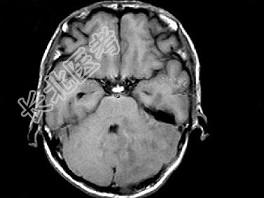

- 单项选择题男,41岁, 左枕部疼痛,右侧肢体乏力, 并渐进性加重半个月,右侧肢体乏力, 行走不稳,根据所提供图像, 最可能的诊断是 ( )

A、(小脑)血管母细胞瘤

B、(小脑)髓母细胞瘤

C、(小脑)炎性肉芽肿

D、(小脑)转移瘤

E、(小脑)星形胶质细胞瘤Ⅰ~Ⅱ级